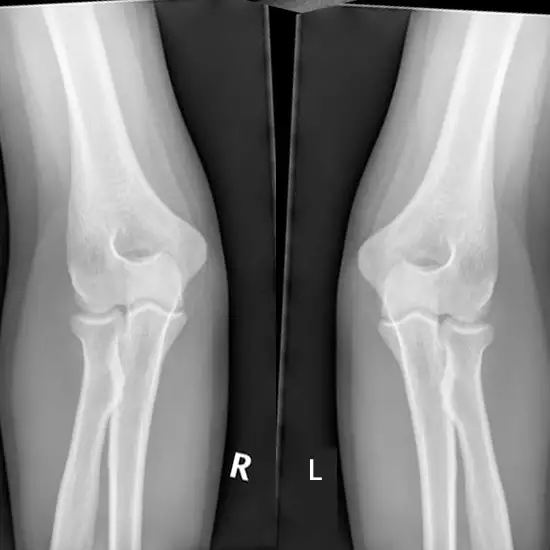

X-ray Both Elbow Joints AP View

An elbow X-Ray AP view is a diagnostic test that provides the images of the inside of your elbow. X-ray of an elbow shows its soft tissues, elbow bone upper- humerus and lower hand bones - radius and ulna and the elbow joint. With the help of X-Ray doctors can assess the calcium in bones.

An elbow X-ray typically consists of three images or more. When necessary, your technologist will come back to realign your elbow. Three different views will be captured: an anterior-posterior view, a lateral view, and an oblique view. Three different angles will also be captured. Inform your technologist if you're in any pain so they can support you during the test.